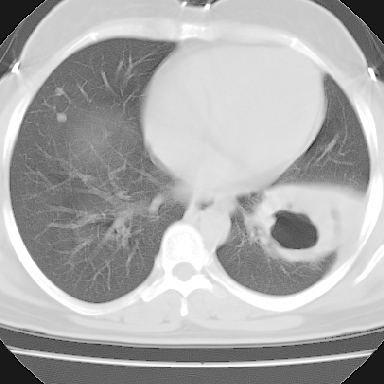

左下肺有空洞,壁厚薄不均,壁结节,两肺多发小结节影,腋窝下可疑淋巴结肿大,综上所述考虑周围性肺癌并两肺转移可能性大,建议穿刺活检。

右肺多发小结节影,边界清楚,符合转移瘤的特点;2、左下肺偏心性空洞影,右侧乳腺内高密度影,需要查体除外右侧乳腺肿瘤;3、腋窝淋巴结肿大,考虑转移。

支持癌性空洞:壁厚,无液平,内壁不规则,外壁呈分叶状,较大,偏心性,壁结节,胸膜凹陷,转移灶。